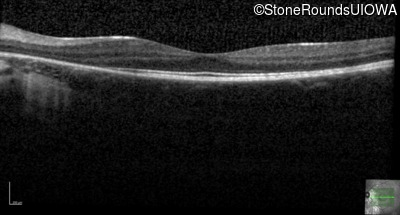

Age at visit: 14 years

This fourteen year old female has had poor vision in dim light since at least age 6.

Age at visit: 15 years

Age at visit: 16 years